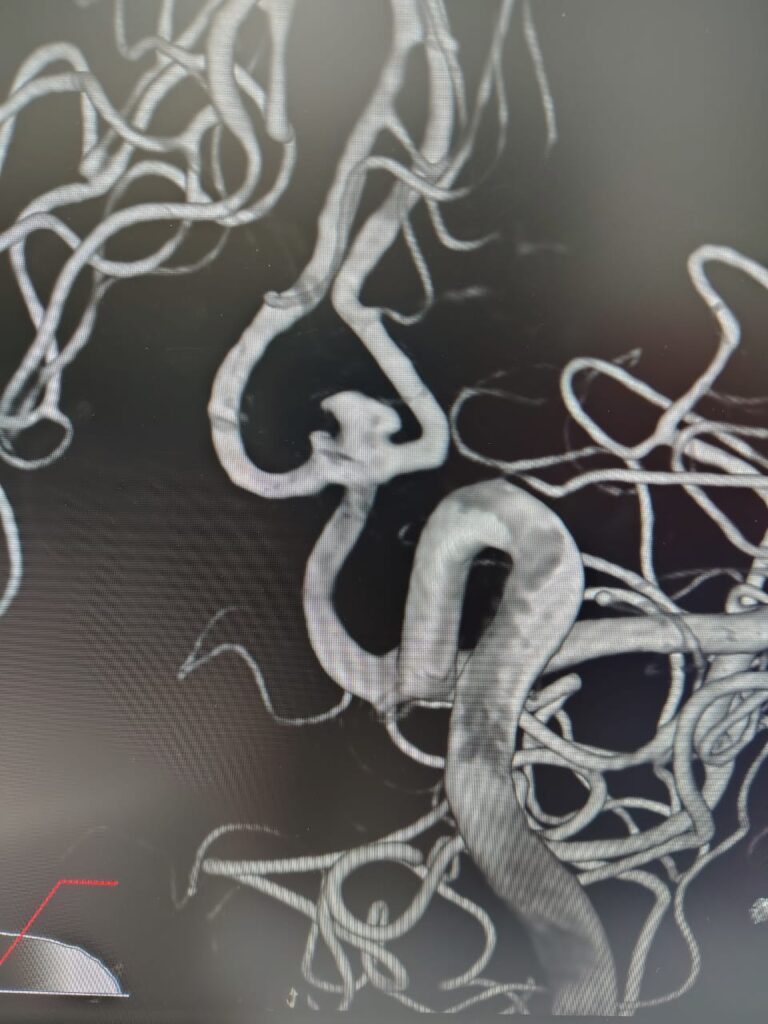

Case 4

Ruptured Brain aneurysm (left ICA communicating segment wideneck aneurysm) treated with Stent Assisted Coiling.

aneurysm cannulated with microcatheter and microwire

Coiling in live case

after complete coiling and stenting

final result complete coiling and Stenting of brain aneurysm